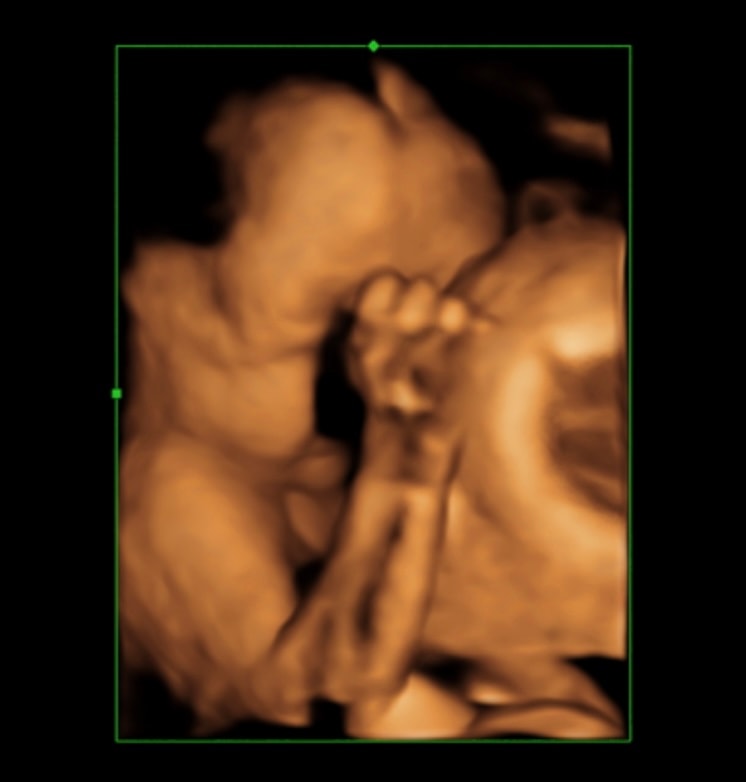

Идем пока ровно 🥰 оба головой вниз . Вес левого - 1148 , вес правого - 1159 . Срок 28,3.

На последнем фото обнимаются лицом к лицу, поэтому и затихли 😂😂 некогда им !